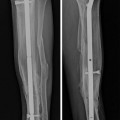

Fig. 5

The pre-built three-level circular frame is placed on the limb (see text)

The surgically obtained correction was maintained by applying a pre-constructed three-level circular external fixator (Fig. 4). Note that the most proximal ring can be “up-sized” by one ring diameter to accommodate the larger calf muscle.